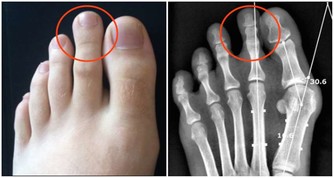

醫師建議乾癬患者務必注意關節症狀,像是早上起床,

關節紅腫脹痛特別明顯的人最好趕緊就醫,以免惡化至關節變形,造成不可挽回的悲劇。